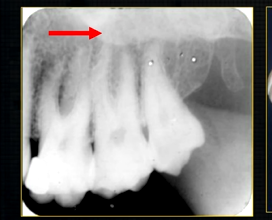

periapical radiograph → posterior maxilla

radiolucent maxillary sinus and radiopaque floor

radiopaque shadow cast by zygoma, hollowed out by maxillary sinus

lower end of the dense, zygomatic bone

posterior aspect of the maxilla - smooth round tuberosity